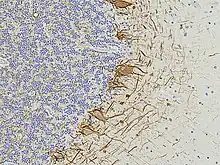

Numerous specific antibodies to neurofilament proteins have been developed and are commercially available. These antibodies can be used to detect neurofilament proteins in cells and tissues using immunofluorescence microscopy or immunohistochemistry. Such antibodies are widely used to identify neurons and their processes in histological sections and in tissue culture. The type VI intermediate filament protein Nestin is expressed in developing neurons and glia. Nestin is considered a marker of neuronal stem cells, and the presence of this protein is widely used to define neurogenesis. This protein is lost as development proceeds.

Neurofilament antibodies are also commonly used in diagnostic neuropathology. Staining with these antibodies can distinguish neurons (positive for neurofilament proteins) from glia (negative for neurofilament proteins).